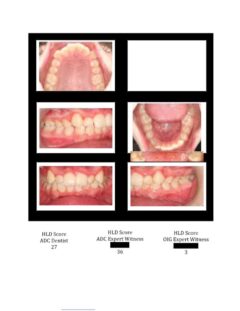

So here again are photos of children’s teeth that were pre-approved for treatment by the state’s Medicaid claims administrator TMHP/ACS, that HHSC-OIG now claims were fraudulently scored by Medicaid dental providers. These cases are from the SOAH hearings that have been completed for Harlingen Family Dentistry and Antoine Dental Center. The SOAH courts found both practices innocent of any allegation of Medicaid fraud or misrepresentation. The photo pages show the attending dentist’s HLD score, the dentist’s expert witness score and the OIG expert’s score.

Antoine Dental Center